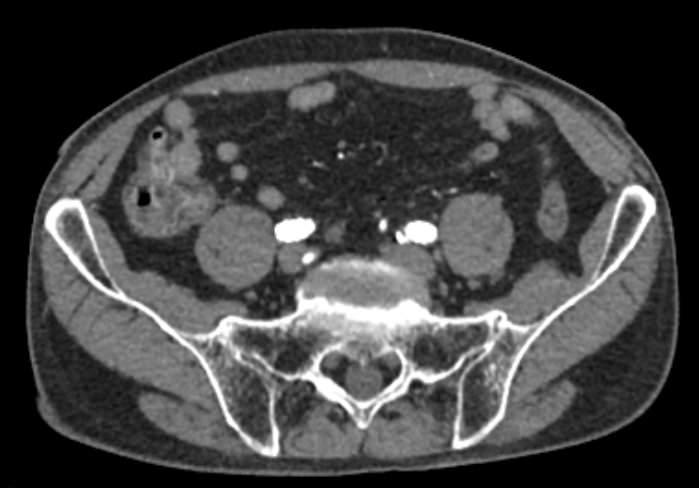

Основные показания для проведения КТ брюшного отдела аорты и артерий нижних конечностей могут включать:

• Стенозы и окклюзии: выявление и оценка степени сужения или блокировки артерий.

• Тромбозы: обнаружение тромбов и оценка их размера и локализации.

• Подготовка к хирургическим вмешательствам: планирование сосудистых операций и вмешательств.

• Оценка послеоперационного состояния: контроль за состоянием сосудов после хирургических вмешательств.